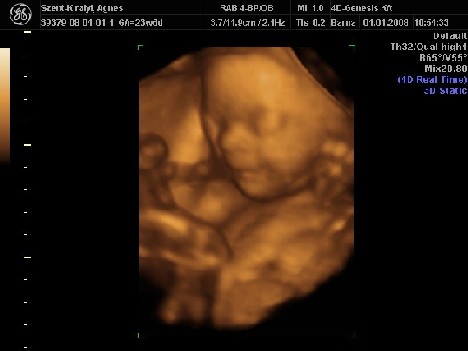

A pocakom akkora, hogy nem tudom, hogy hova tud még nőni 3 hónap alatt. A mérete alapján már mehetnék szülni. Majd teszek fel képet ha sikerül csinálnom.